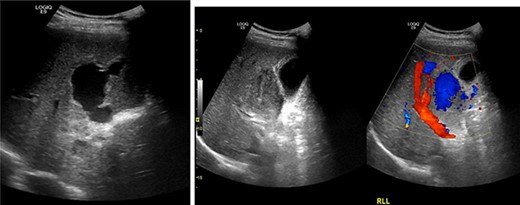

Resuscitation was carried on with 2 l of normal saline and two PRBC units to stabilize the patient. The computed tomography (CT) scan identified Grade 4 liver injury with hemoperitoneum (Fig. 2). Subsequently, the multiple bone fractures underwent surgical fixation, and post-operatively, he was hemodynamically stable. On the fifth day after admission, repeated CT scan demonstrated the liver injury with no evidence of hepatic pseudoaneurysm (Fig. 3). The patient remained stable with tolerated feeding with no abdominal pain or distension. On the Day 17, he developed abdominal pain mainly in the epigastrium, which was associated with nausea and deep epigastric tenderness. Abdominal ultrasound (US) (Fig. 4) and CT scan (Fig. 5) revealed complex, large intraparenchymal hepatic pseudoaneurysm (measuring about 58 × 41 × 30 mm) related to the left hepatic artery Segment 4 branch with surrounding hematoma located mainly at segment 4B/A ,and there was another tiny pseudoaneurysm seen at Segment 4A. Selective angiography confirmed the diagnosis of pseudoaneurysm with multiple blood supplies from Segment IV and Segment II.